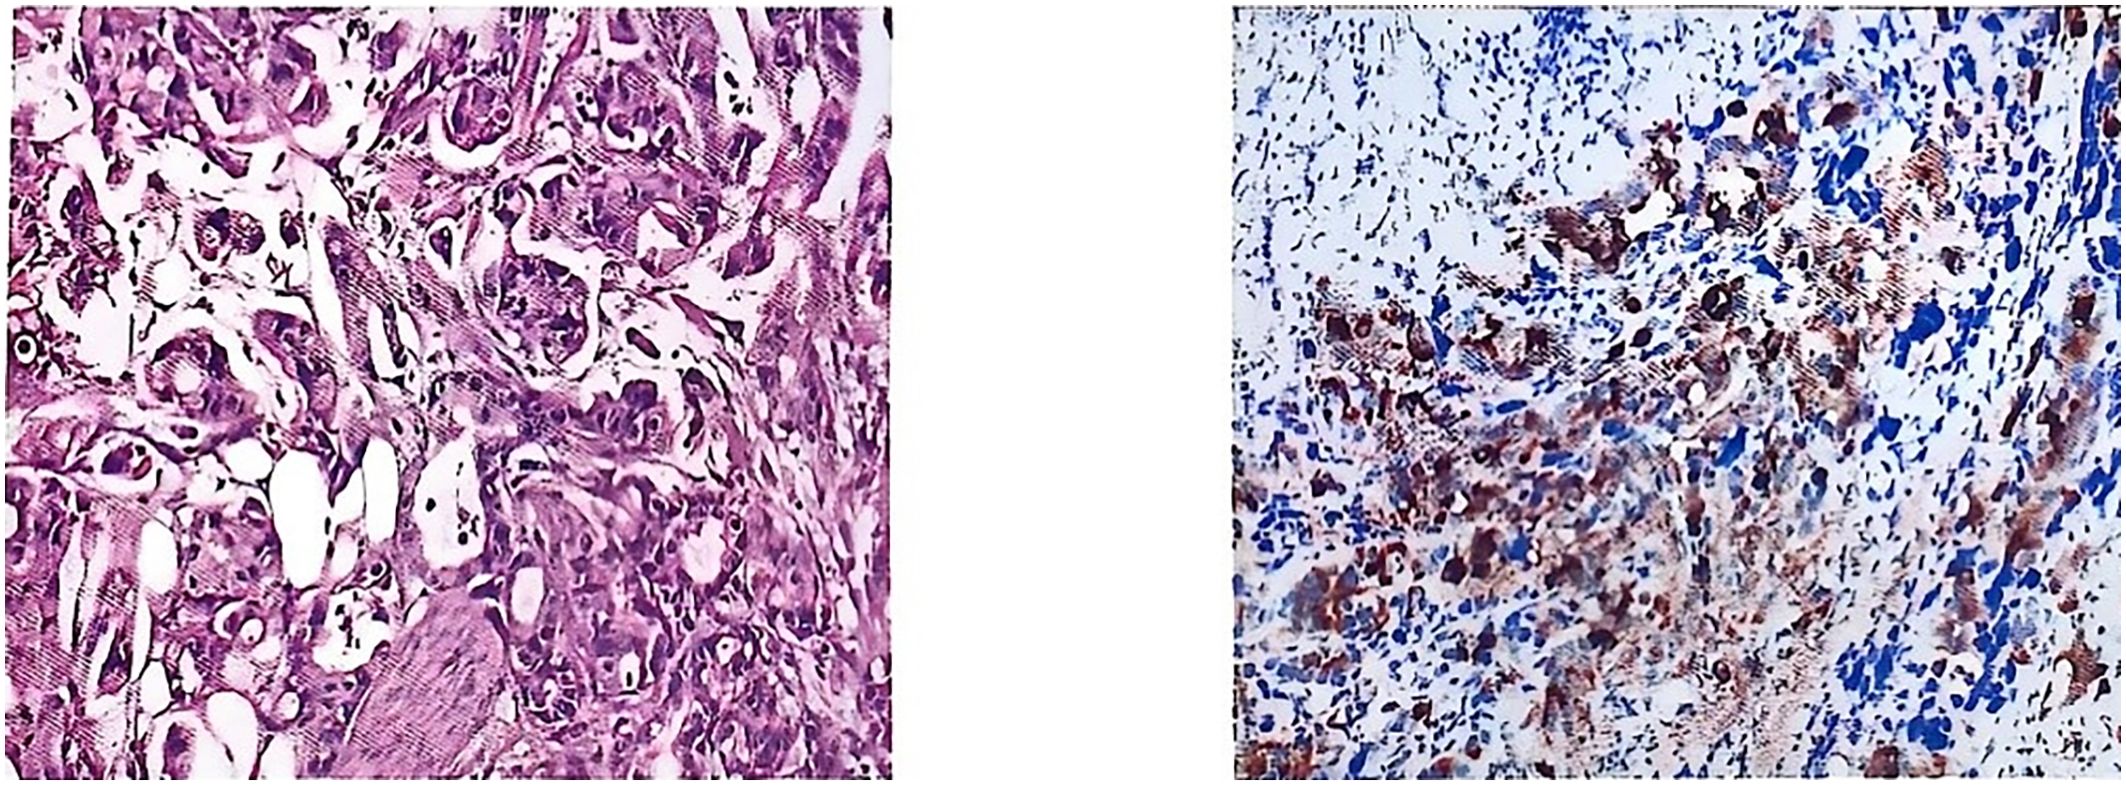

Postoperative pathology was consistent with metastasis of gastric adenocarcinoma. Pathological diagnosis: (left side) infiltration of poorly differentiated tubular adenocarcinoma in the testis and epididymis, with the maximum diameter of the tumor being approximately 4.0 cm; nerve bundle invasion (+), vascular invasion (+); no cancerous cells were observed in the margins of the surgical incision; the combination of the immunophenotyping examination results suggested the possibility of upper gastrointestinal tract origin, so please correlate with the clinical history. Immunomarkers: MUC5AC (+), CK7 (+), CK20 (+), CDX-2 (foci +), CEA (+), HER2 (-), TTF-1 (-), Ki-67 (+, about 50%) (Figure 3).

Figure 3

HE-stained section showing tissue architecture with purple-blue nuclei and pink cytoplasm/stroma. It shows microscopic tissue sections. The left panel displays a pink-stained tissue section with dense cellular structures. The right panel shows a tissue section with blue and brown staining, with more scattered cellular elements.

Figure 3. Postoperative pathology.